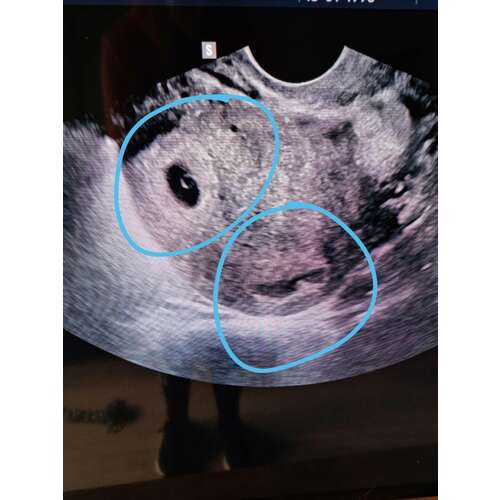

Nee hoor, dat was mijn zwangerschap, inmiddels zijn de meiden bijna 8 maanden.

Ik vond de zwangerschap lichamelijk heel zwaar, ben op 12 weken al gestopt met werken. Uiteindelijk wel kunnen uitdragen tot 37 weken.